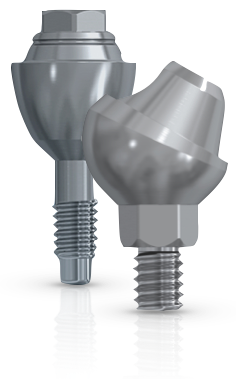

Рентген имплантов Alpha Bio: диагностика и качество